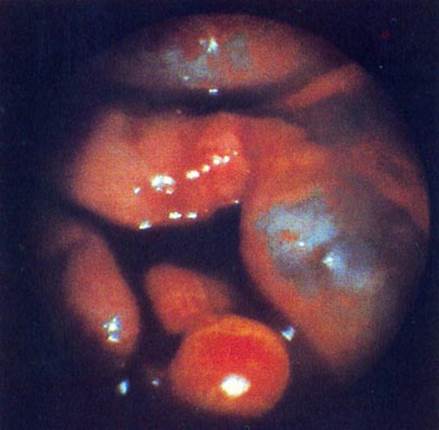

Больная В., 36 лет, обратилась к врачу женской консультации с жалобами на боли в животе накануне менструации, мажущие кровянистые выделения накануне и после менструации.

В л агалищное обследов а н и е: наружные половые органы развиты правильно. Влагалище — рожавшей женщины. Шейка матки имеет цилиндрическую форму, не деформирована. Наружный зев закрыт. Матка шаровидной формы, крупнее нормы, безболезненная при пальпации

Придатки не определяются. Зона их болезненна.

Проведена гистерография. Данные гистерографии представлены на рисунке.

Ваш диагноз:

При лапароскопии:

разлитой перитонит; //

миома матки; //

внематочная беременность; //

спаечный процесс малого таза; //

+эндометриоидные гетеротопии малого таза